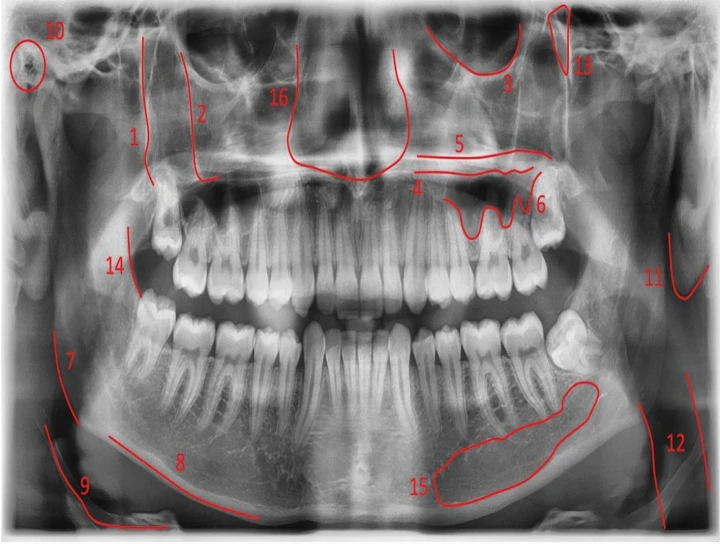

Post-Processing of Panoramic Radiographs: Demystifying Its VeracityPanoramic radiography is a widel...